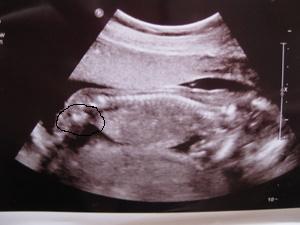

Mercy: Nagyon cuki a kis szégyenlős babód, hogy direkt eltakarta magát. Örülök, hogy minden rendben, + hogy végre érzed a mocorgást éshát azok a tappancsok az UHképen.... halál édes!

(Jah... és mostmár biztos, hogy egyedül van!

)